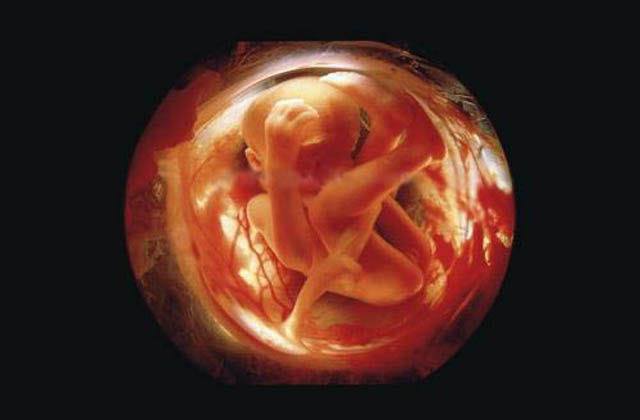

![]() |

Eight weeks.The rapidly-growing embryo is well protected in the foetal sac |